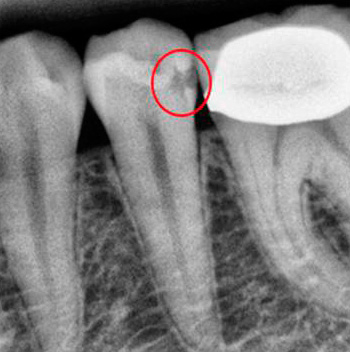

Ad esempio, nella radiografia in basso, una cavità cariata nel dente è chiaramente visibile, che non è stata rilevata con un semplice esame visivo:

Una radiografia è particolarmente utile per rilevare la ricorrenza della carie, nonché la carie radicolare e la carie prossimale. Ad esempio, ecco una foto in cui puoi vedere come appare la carie approssimativa nell'immagine: